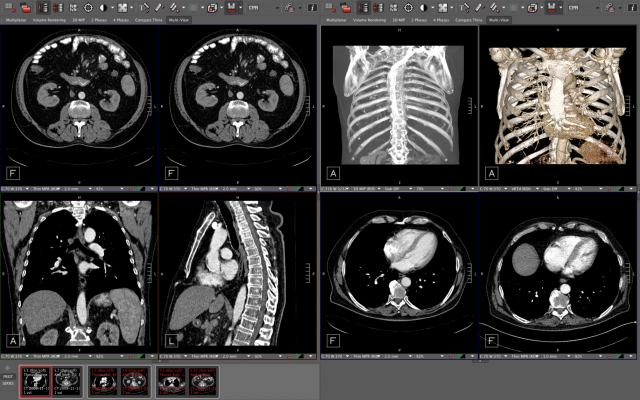

Healthcare institutions are seeking modern, flexible solutions and have a heightened awareness of security due to the increasing threat of malware and ransomware attacks. These factors, in combination with the relentless growth of imaging datasets, continue to present architectural and performance hurdles for imaging organizations reliant on legacy PACS with 'compress and send' limitations and inferior server-side technology.

"Today's Enterprise Imaging challenges institutions with constantly evolving requirements," explained Malte Westerhoff, Ph.D., Visage Imaging Co-Founder and Chief Technology Officer. Westerhoff continued, "At Visage, we continue to implement leading design principles with Visage 7 that enhance capabilities, improve performance and tighten security. This allows our customers to remain a step ahead of their increasing clinical needs and the threats that they must navigate. Visage continues to innovate with significant velocity, rapidly getting new features into clinical use. With Visage 7 Live Connect, we're enabling radiologists to easily share images with referring physicians during interpretation, without disruption to diagnostic reading workflow. The simplicity of collaboration will encourage radiologists to utilize imaging communications in ways that were previously not thought possible, to include the potential for collaboration with patients and their imaging."

- Visage 7 Live Connect. Visage 7 Live Connect empowers collaboration, making real-time communications easy. Radiologists will be able to immediately and securely collaborate, sharing images with referrers directly from Visage 7 during interpretation workflow. The radiologist will simply pass a secure link and session code to all intended recipients for real-time viewing from any HTML browser using any of their preferred devices (e.g., desktop, mobile, tablet). Even though radiologists typically use multiple high-resolution diagnostic displays, and referring physicians may use a single display or a mobile device, Visage 7 Live Connect is not restricted due to any potential display or device type mismatch. Instead, collaborative image viewing is optimally focused on the radiologist's active viewer, does not require recipient users have any installed software or account(s) on Visage 7, and all recipients are able to view shared cursor movements from one or multiple screen share participants.

- Transcatheter Aortic Valve Replacement (TAVR) Planning. Demonstrated as a works-in-progress, Visage 7 supports a new Triangle tool for TAVR planning. This tool automatically repositions all of the MPR viewers, so the axial view is in plane with the valve where the leaflets join. This rapidly allows the radiologist to drop 3 points simplifying the capture of TAVR planning measurements.